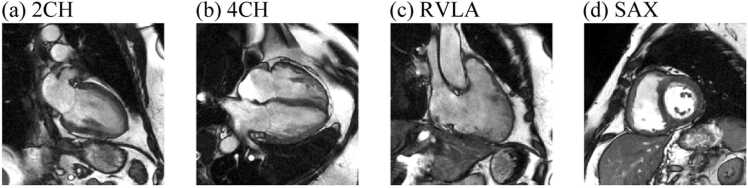

Methods: We constructed an explainable convolutional neural network (CNN) taking cardiac MR cine series from four different views as input to predict mean pulmonary artery pressure (mPAP). The model was trained and evaluated on 1646 examinations. The model's attention weight and predictive performance associated with each frame, view, or phase were used to judge its importance. Additionally, the importance of each cardiac chamber was inferred by perturbing part of the input pixels.

Results: The model achieved a Pearson correlation coefficient of 0.80 and R2 of 0.64 in predicting mPAP and identified the right ventricle region on short-axis view to be especially informative.